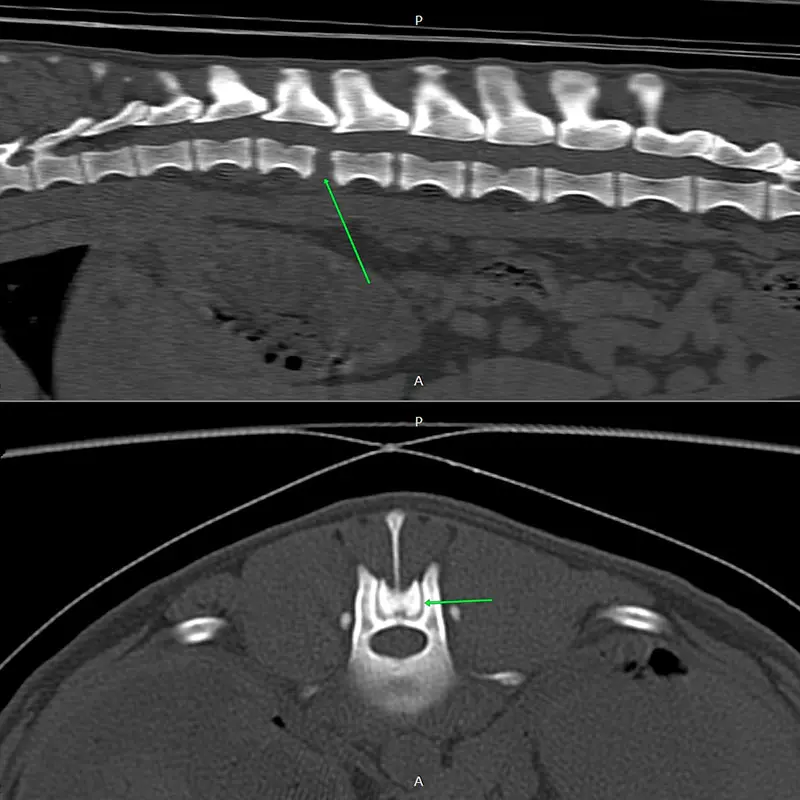

We have been using the system for years, and clinical experience greatly supports its reliability, even in difficult, challenging situations. It is excellent for stabilizing the spine, especially in the thoraco-lumbar region. If the connecting rod is placed ventrally from the articular processes, the screws are placed in the vertebral body at a 45-degree angle at the base of the transverse processes, so that they grip the largest possible bone material. (see CT images). Up to 2 clamps can be attached to a vertebral body from one side. Compared to other, more complex, multi-piece spinal stabilization systems, it is thinner and fits better on the surface of the bone. The screw axis is located ont he side of the axis of the connecting rod (the rod and the screw are not located on top of each other), the clamps can be rotated and slid, so that the largest possible bone stock can be freely accessed during surgery.

In our case, we stabilized the T13-L1 vertebral luxation of a 4-year-old dachshund, where the ligament system of the vertebral body was damaged during a car accident.